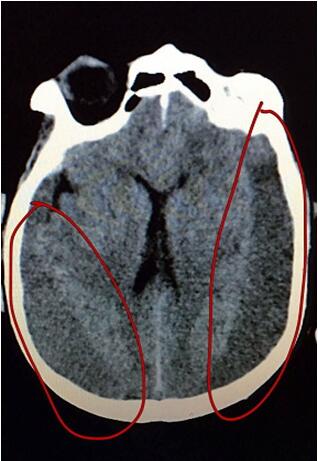

患者在外院行頭顱MRI提示雙側(cè)額顳慢性硬膜下血腫并積液,主管醫(yī)生段威和宋俊杰副主任醫(yī)師仔細看了片子后,發(fā)現(xiàn)雙側(cè)硬膜下出血高達100ml??紤]到患者年齡大,開顱手術(shù)相對風險大,遂決定暫采取血腫腔鉆孔引流的方式。家屬了解病情后焦灼不已,宋醫(yī)生和段醫(yī)生迎難而上,為患者進行了全面的檢查與評估。經(jīng)過細致的術(shù)前討論及充分的術(shù)前準備,10月26日,醫(yī)生為患者在局麻下行雙側(cè)額顳慢性硬膜下血腫鉆孔引流術(shù),手術(shù)順利完成。